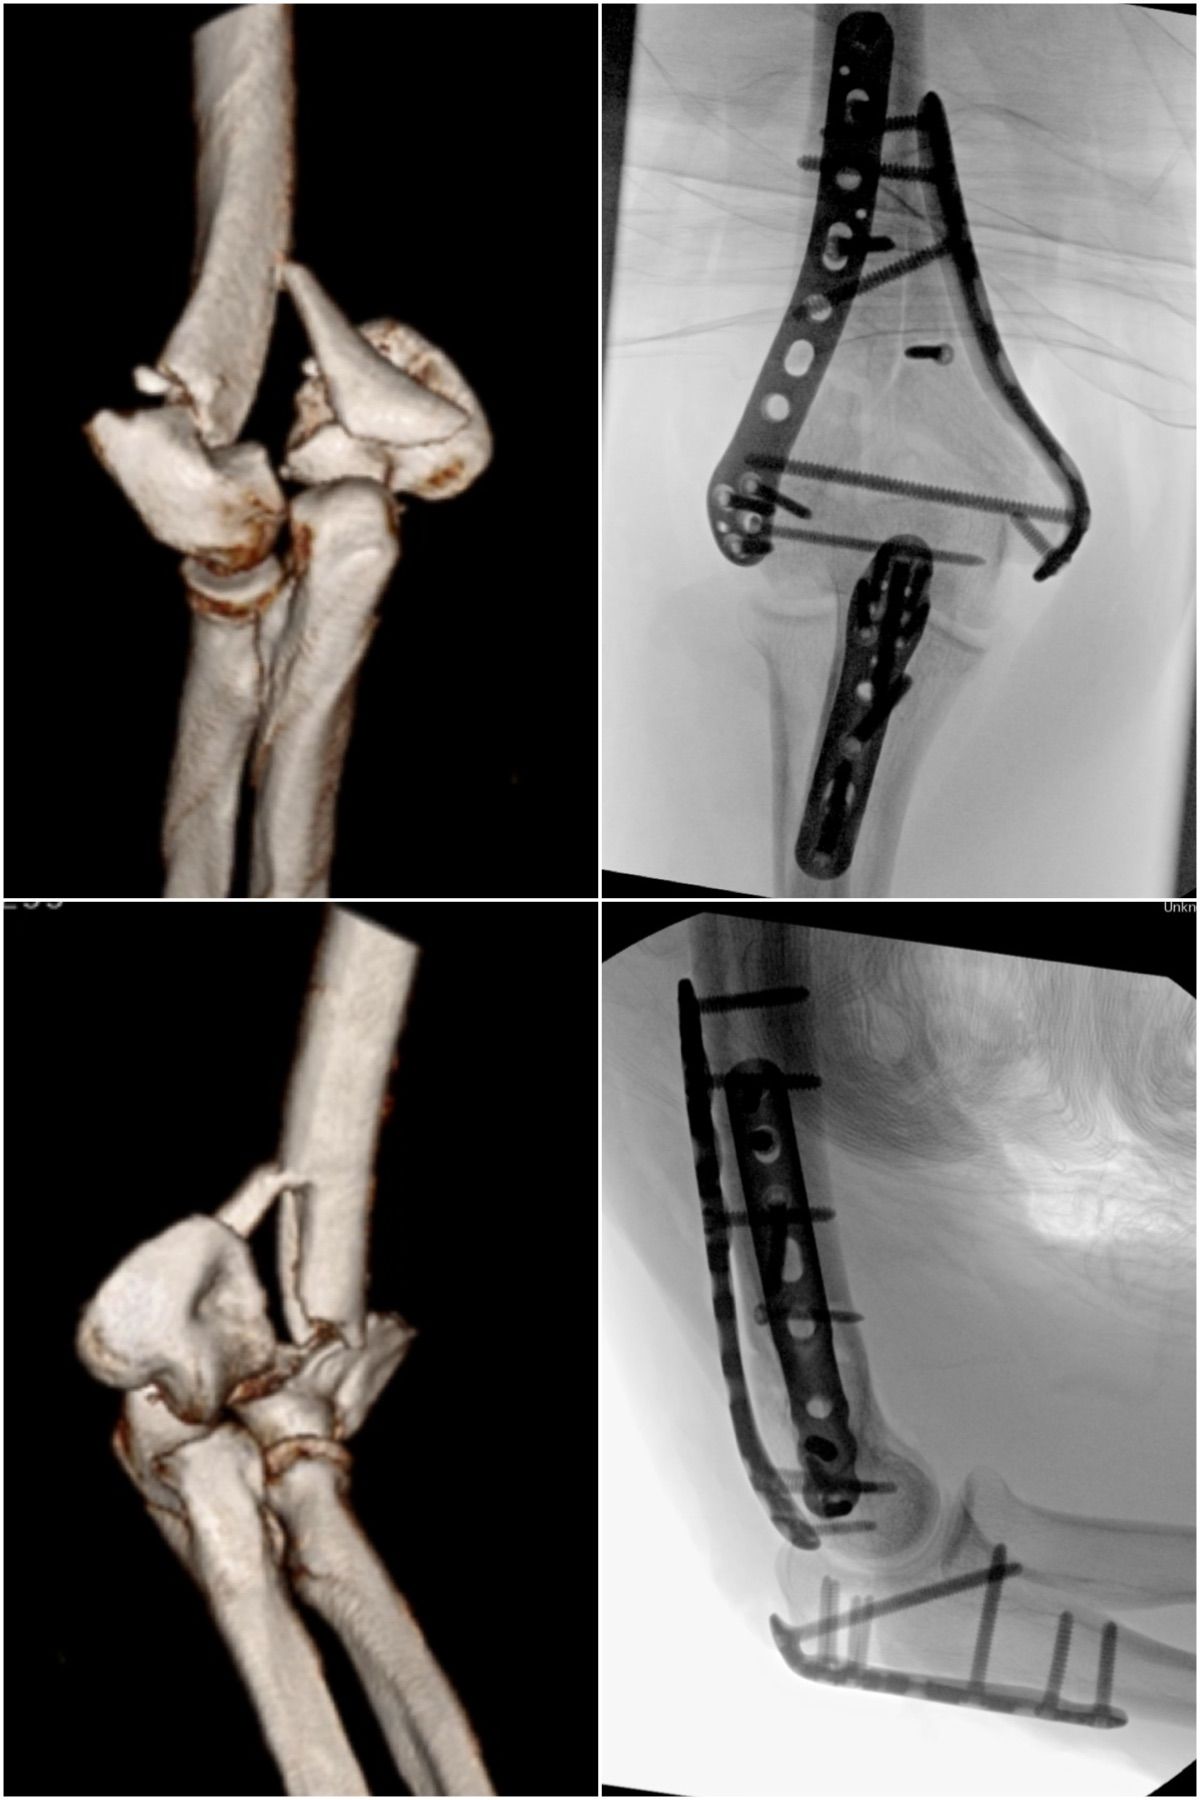

Se especializa en Síndrome del Manguito Rotador, Artroscopía de Hombro, Luxación de Hombro, Epicondilitis Lateral (Codo de Tenista), Fractura de Clavícula, Disyunción Acromioclavicular, Fracturas de Codo.

Conferencista. Tríada Terrible del Codo. II Jornadas de Traumatología. Hospital Universitario de Caracas (HUC). Caracas, Venezuela. 2015